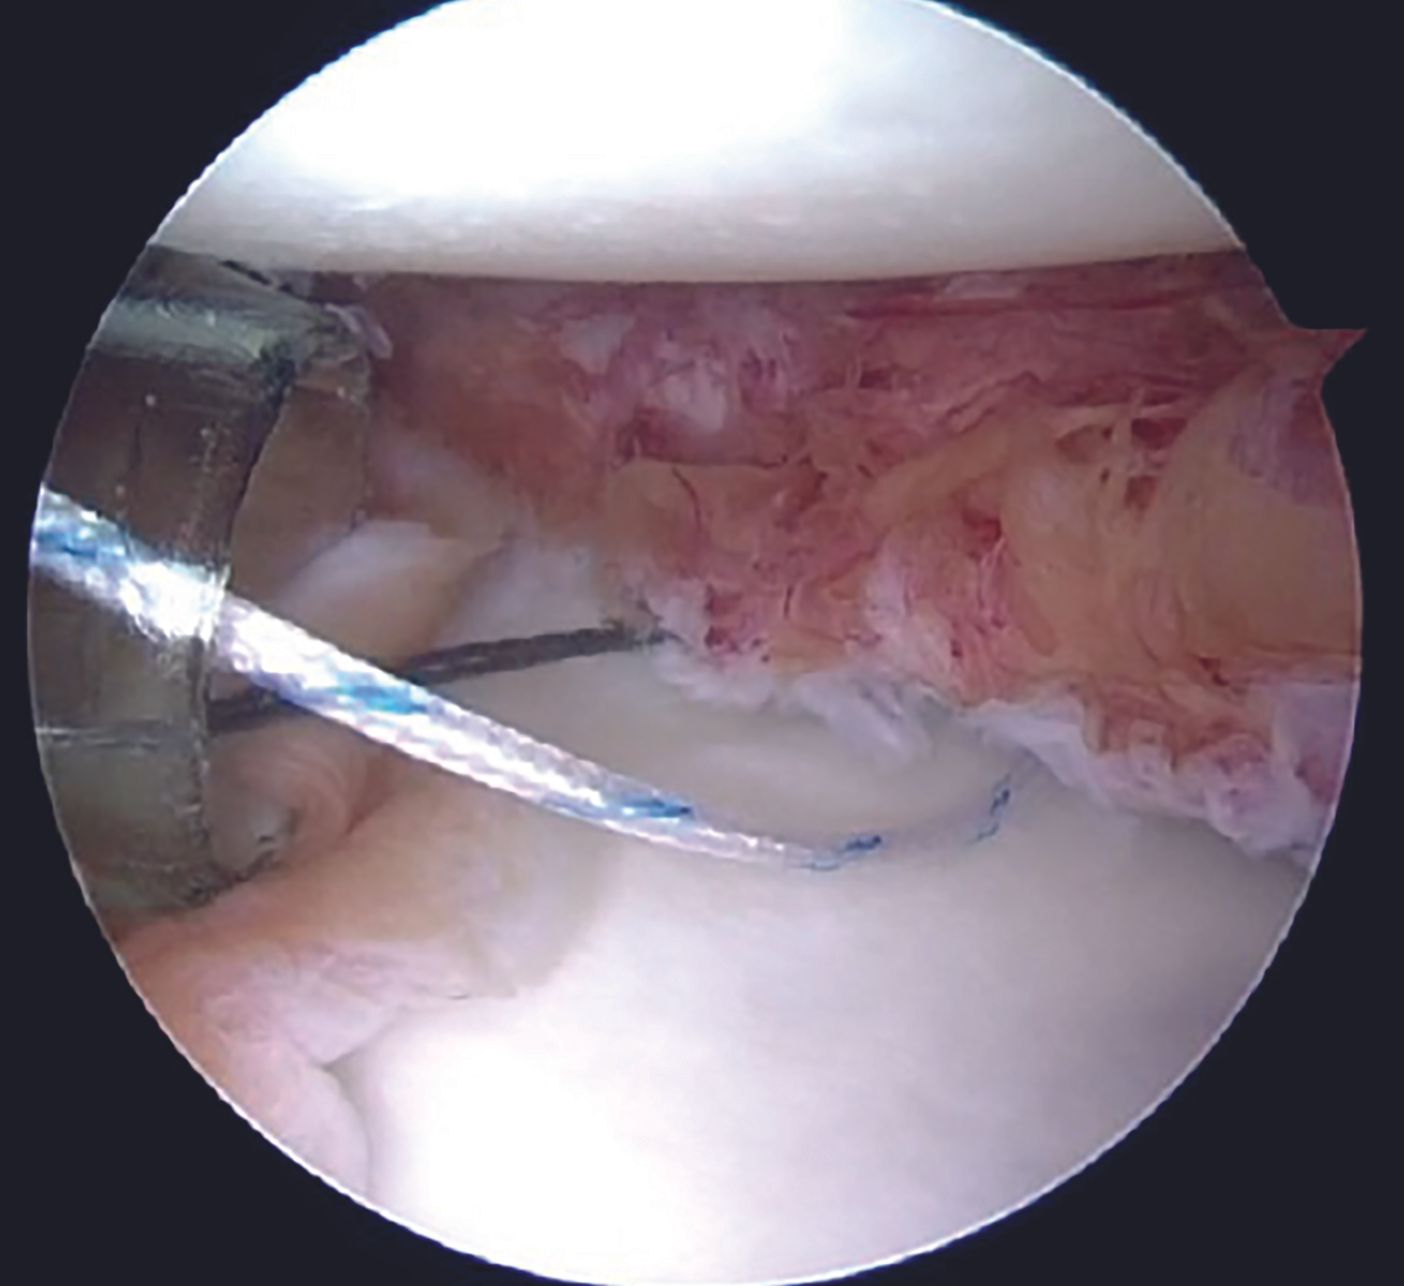

One of the tapes is then retrieved through the posterior portal with a tape retriever (Figure 11) and then shuttled through the labral tissue using a suture passer device (Figure 12,13).

A grasper can be utilized for holding the labral tissue in order to allow easy passage of the suture passer device. With both the tapes in the AI portal, a sliding Duncan loop knot is first tied (Figure 14), followed by at least three half hitches.